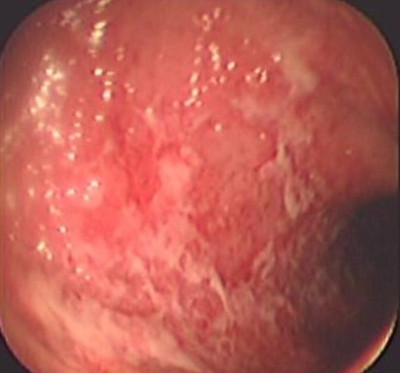

Colitis ulcerosa crónica inespecífica

Envíado por Dr. Carlos Ernesto Arévalo